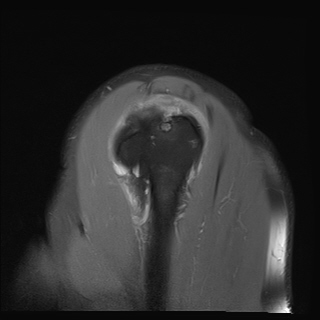

±Ø»ó°Ç ±ÙÀ§ºÎ ±Ø»ó°Ç ³»ÃøÀÇ Àú¿¡ÄÚ ºÎÁ¾°ú Á¡¾×³¶ ºÎÁ¾ÀÌ °üÂûµÊ(±×¸² 5).

±Ø»ó°Ç ¿øÀ§ºÎ ±Ø»ó°Ç ºÎÂøºÎ ÀÛÀº ÆÄ¿­ÀÌ °üÂûµÊ(±×¸² 6).